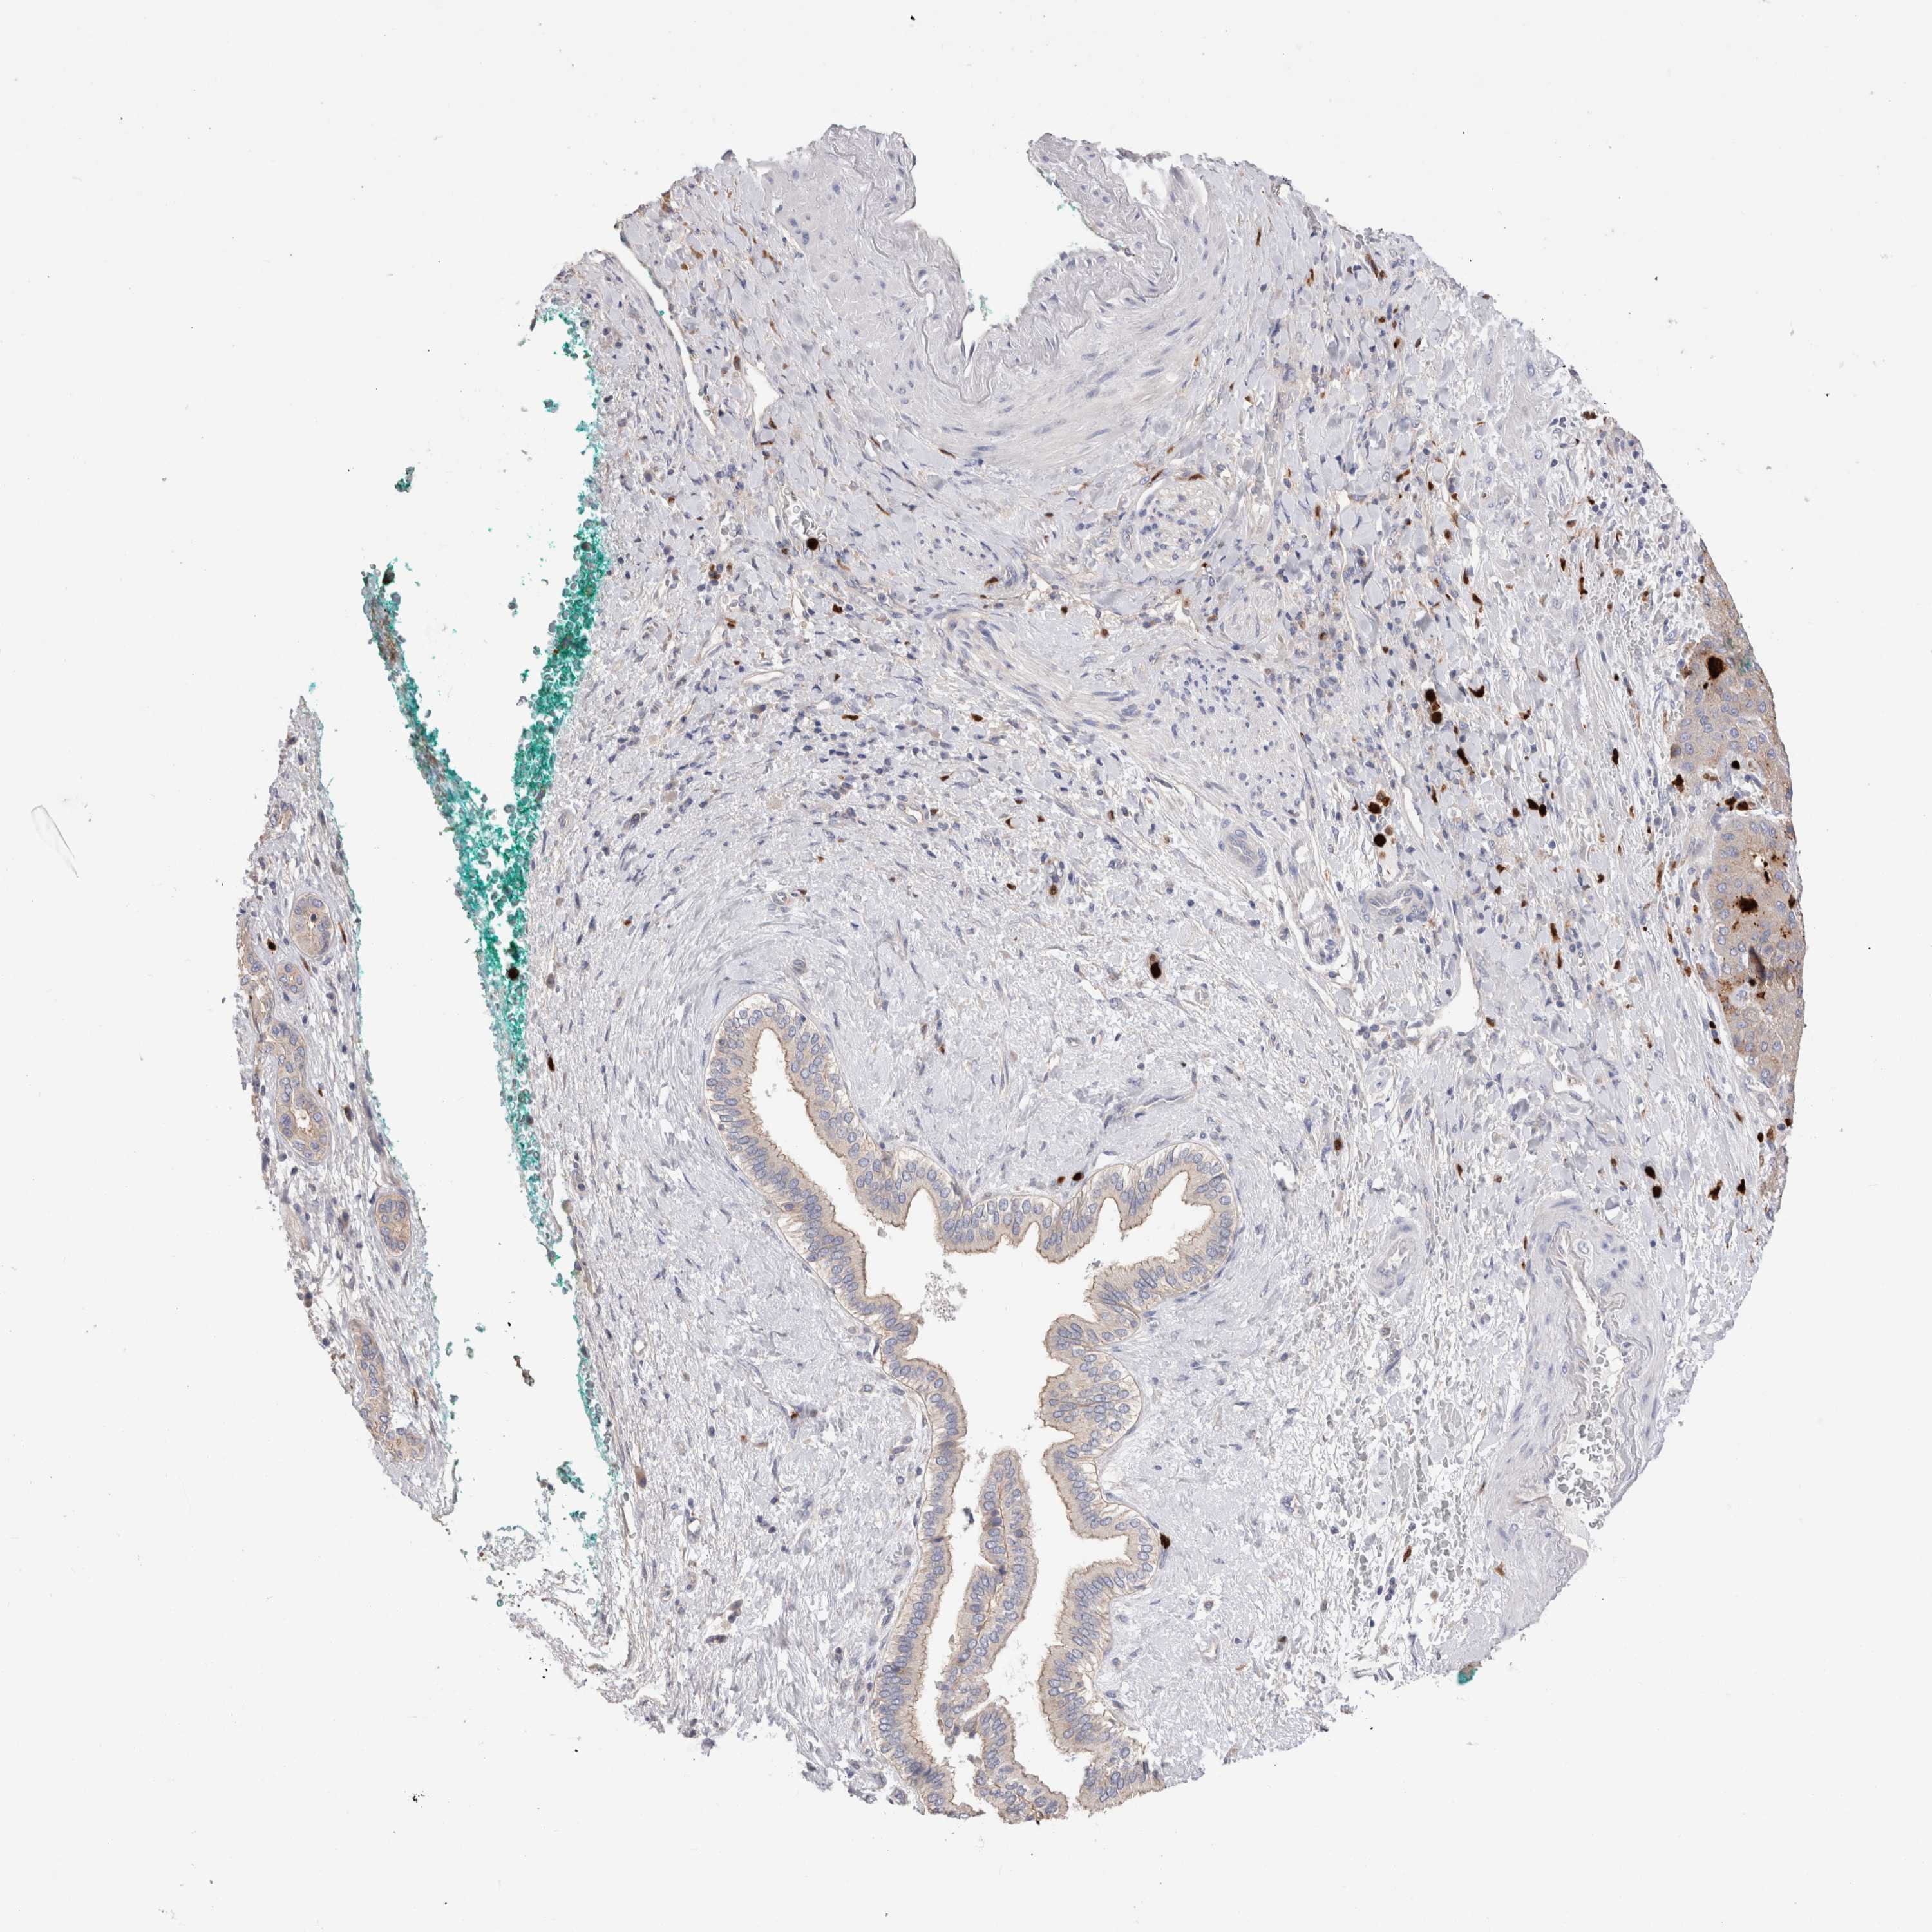

LIVER CANCER - Protein expressioni

A mouse-over function shows sample information and annotation data. Click on an image to view it in a full screen mode. Samples can be filtered based on level of antibody staining by selecting one or several of the following categories: high, medium, low and not detected. The assay and annotation is described here.

Note that samples used for immunohistochemistry by the Human Protein Atlas do not correspond to samples in the TCGA dataset.

Antibody stainingi

Antibody staining in the annotated cell types in the current human tissue is reported as not detected, low, medium, or high, based on conventional immunohistochemistry profiling in selected tissues. This score is based on the combination of the staining intensity and fraction of stained cells.

Each image is clickable and will lead to virtual microscopy that enables deeper exploration of all samples and also displays staining intensity scores, fraction scores and subcellular localization as well as patient and tissue information for each sample.

Antibody HPA024199

Staining

High

Medium

Low

Not detected

Intensity

Strong

Moderate

Weak

Negative

Quantity

>75%

75%-25%

<25%

None

Location

Nuclear

Cytoplasmic/membranous

Cytoplasmic/membranous,nuclear

Cholangiocarcinoma

Carcinoma, Hepatocellular, NOS